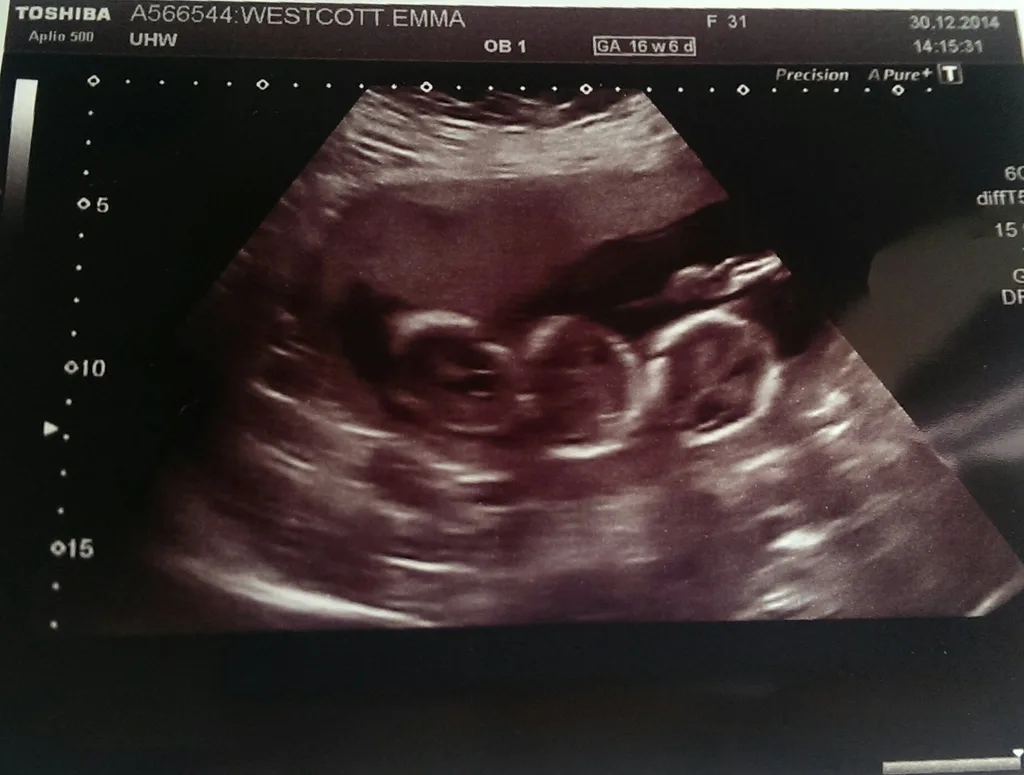

“I can see a heartbeat,” he said, pointing at the screen. “And there’s a second one. And a third!”

Relief quickly gave way to shock. “Three babies?” I gasped. “I’m having triplets?”

A few weeks later we found out we were expecting three boys, and it made everything seem even more real – now our babies had identities. We were both glad they were boys as we thought it was important for Dylan to have male company.

At 32 weeks, my gorgeous baby boys were born via C-section. Ben weighed 1.9kg, Eli weighed 2.1kg, and Max, 2kg. They were a healthy trio and a really good weight for triplets.